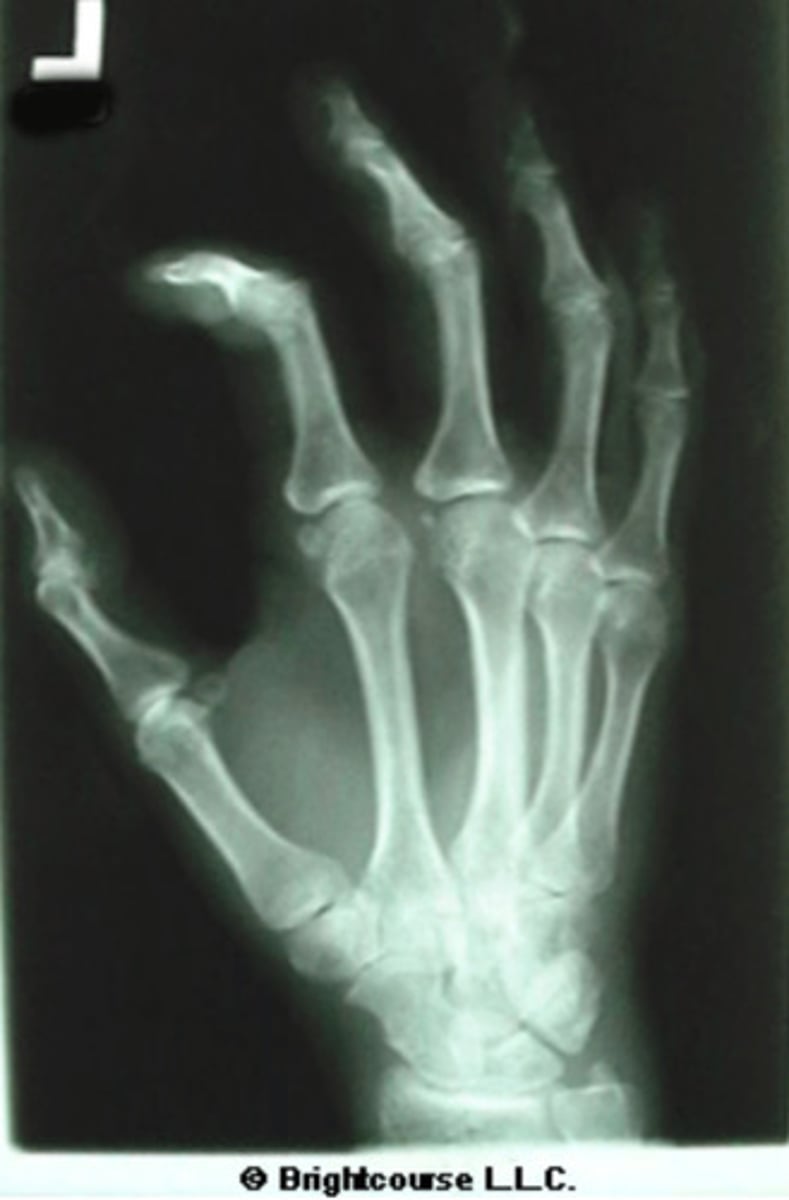

Internal oblique hand

What is the name of the radiographic projection?